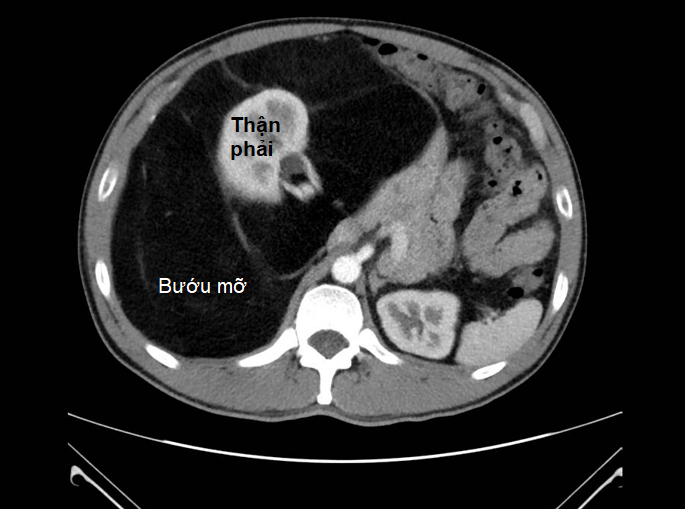

| CT bụng của bệnh nhân cho thấy bướu choán toàn ổ bụng, thận phải đã bị bướu mỡ bao xung quanh |

BS.CKII Nguyễn Phúc Minh, Trưởng khoa Ngoại tiêu hóa là người trực tiếp phẫu thuật cho anh T. Bác sĩ Minh cho biết: “Kết quả chụp MRI bụng cho thấy khối bướu có đường kính lên đến 40 cm, cấu trúc tương đồng với mô mỡ, chiếm gần toàn bộ ổ bụng và bao quanh thận phải. Nghiêm trọng hơn, khối bướu dính và chèn ép các mạch máu lớn như động mạch, tĩnh mạch chủ bụng và các mạch máu lân cận làm suy giảm chức năng thận”.